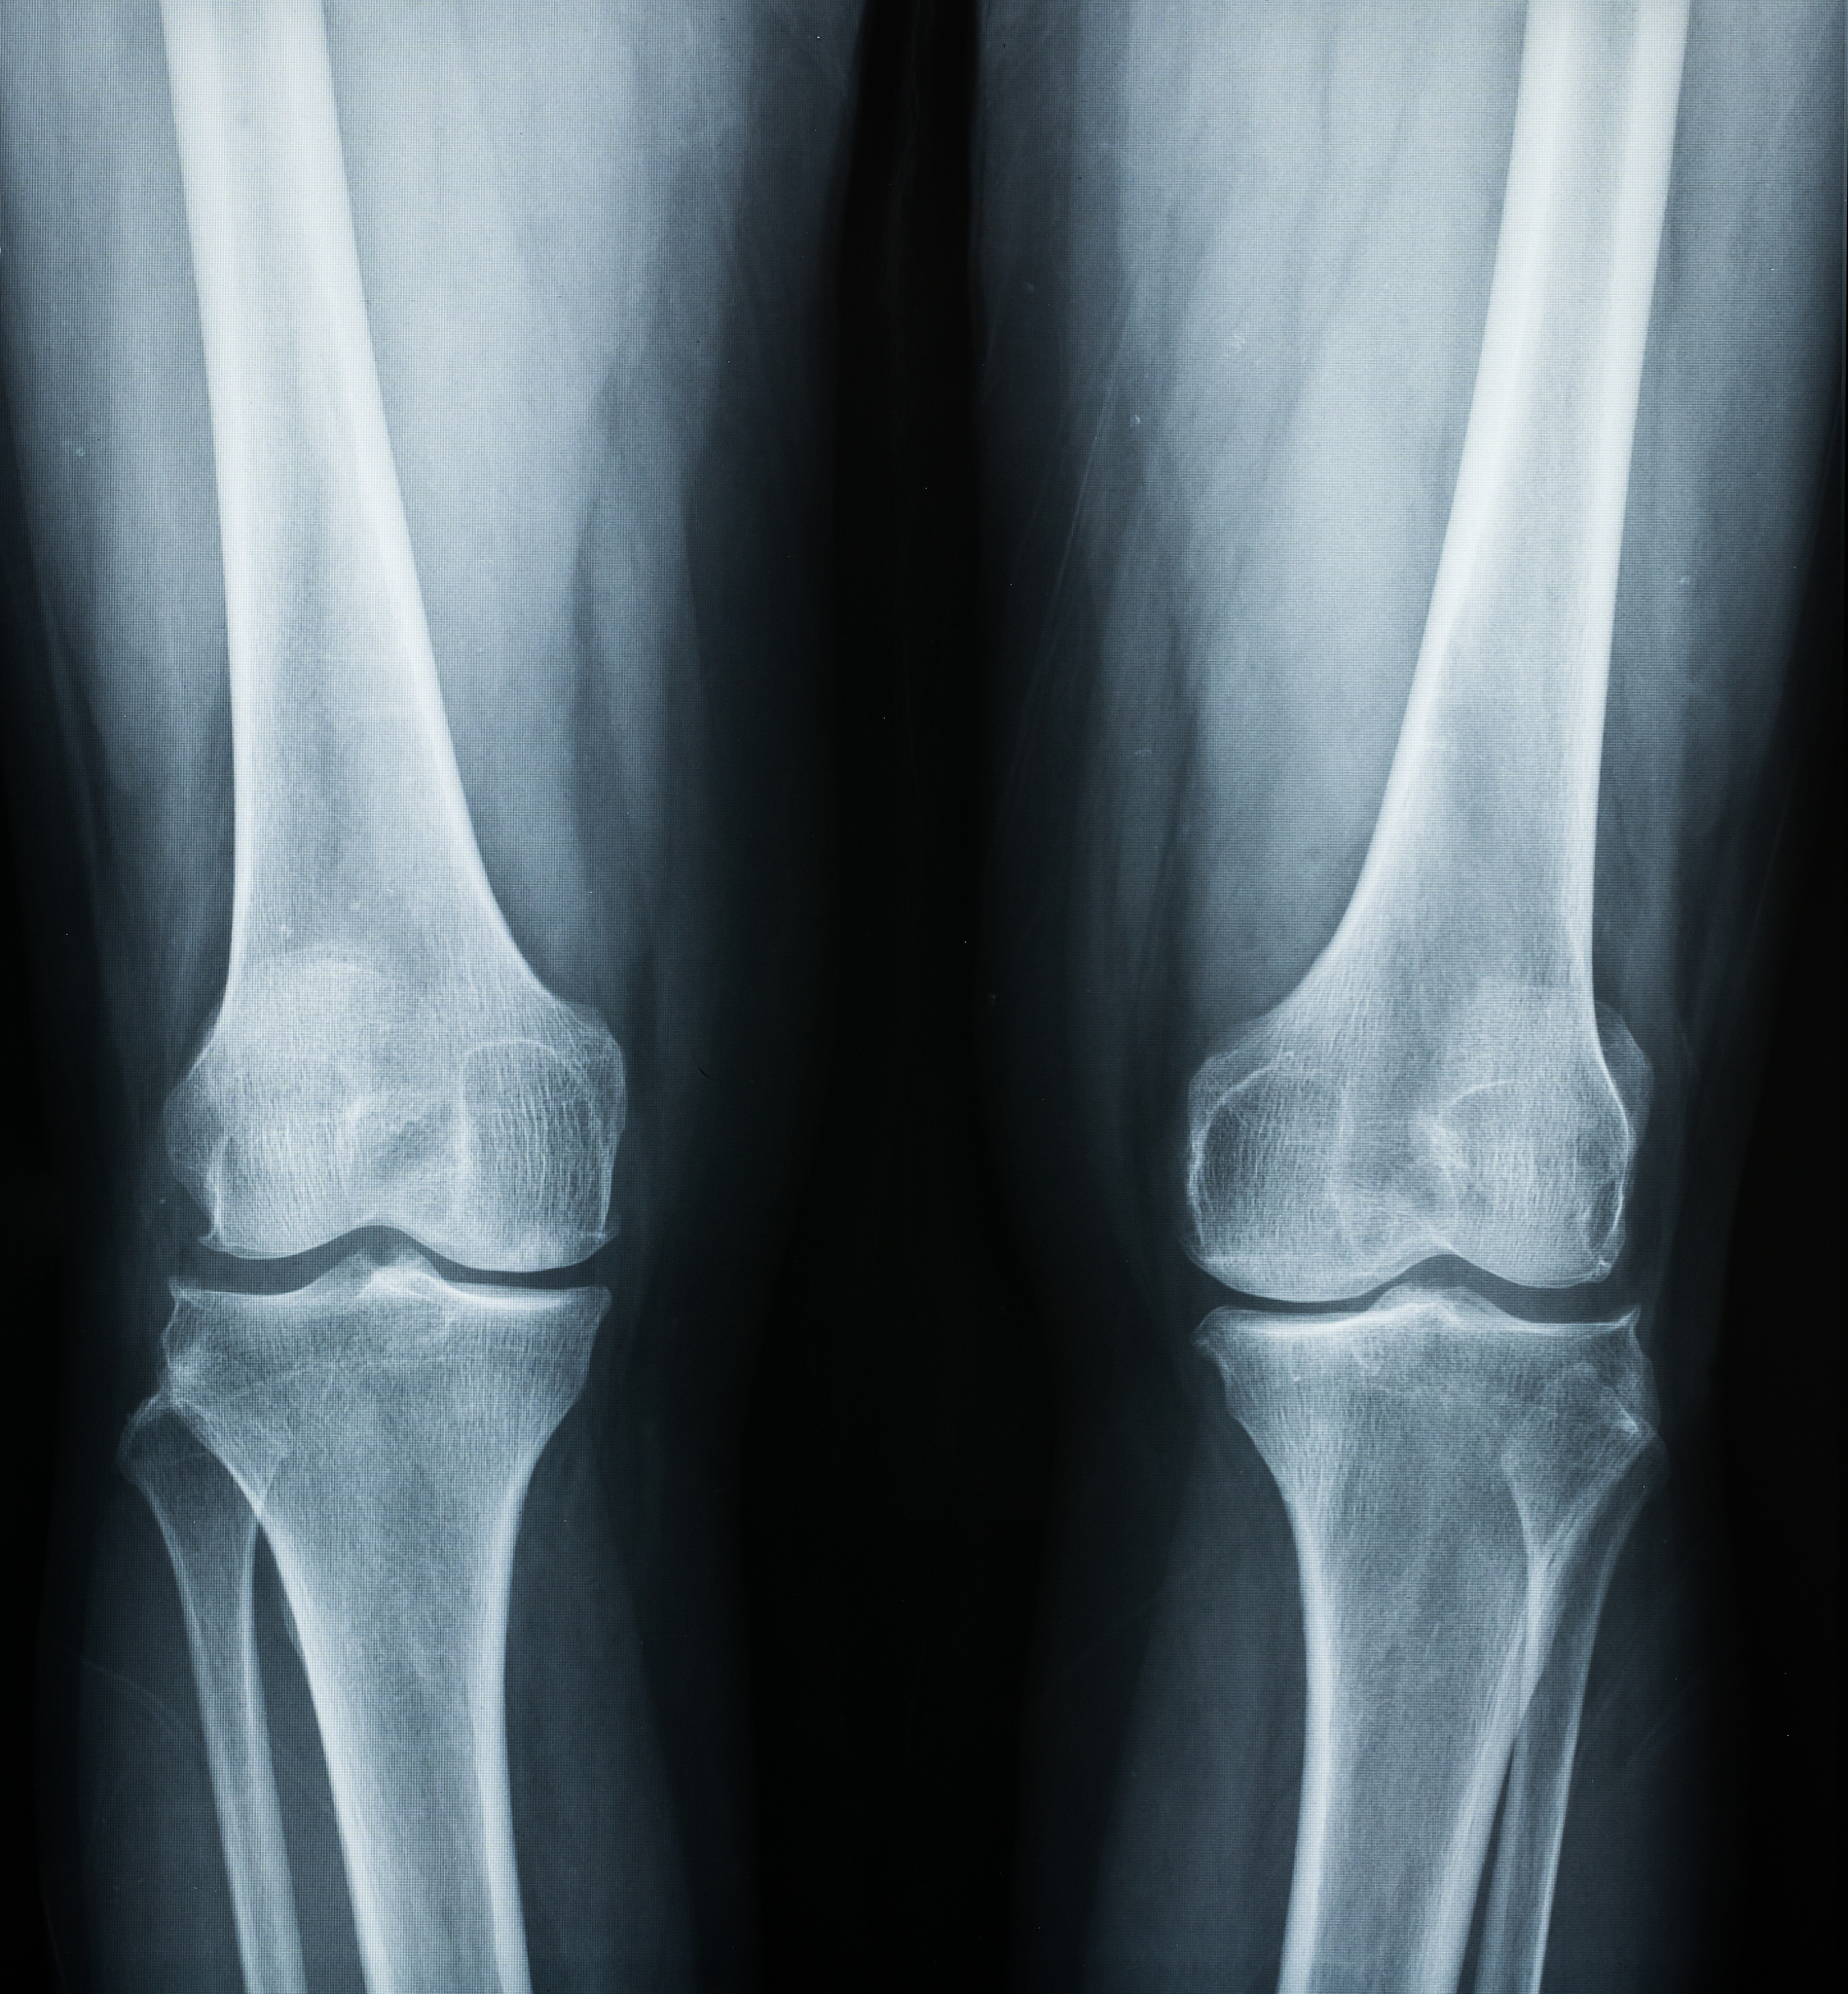

右胫骨平台粉碎性骨折合并前交叉韧带撕脱? 手术治疗方案详解

右胫骨平台粉碎性骨折和前交叉韧带撕脱是两种常见的严重膝关节损伤。此类损伤通常需要进行手术治疗以恢复关节的稳定性和功能。本文将详细介绍在腰硬联合麻醉下进行右胫骨平台粉碎性骨折切开复位内固定+前交叉韧带止点撕脱修补术的具体措施。